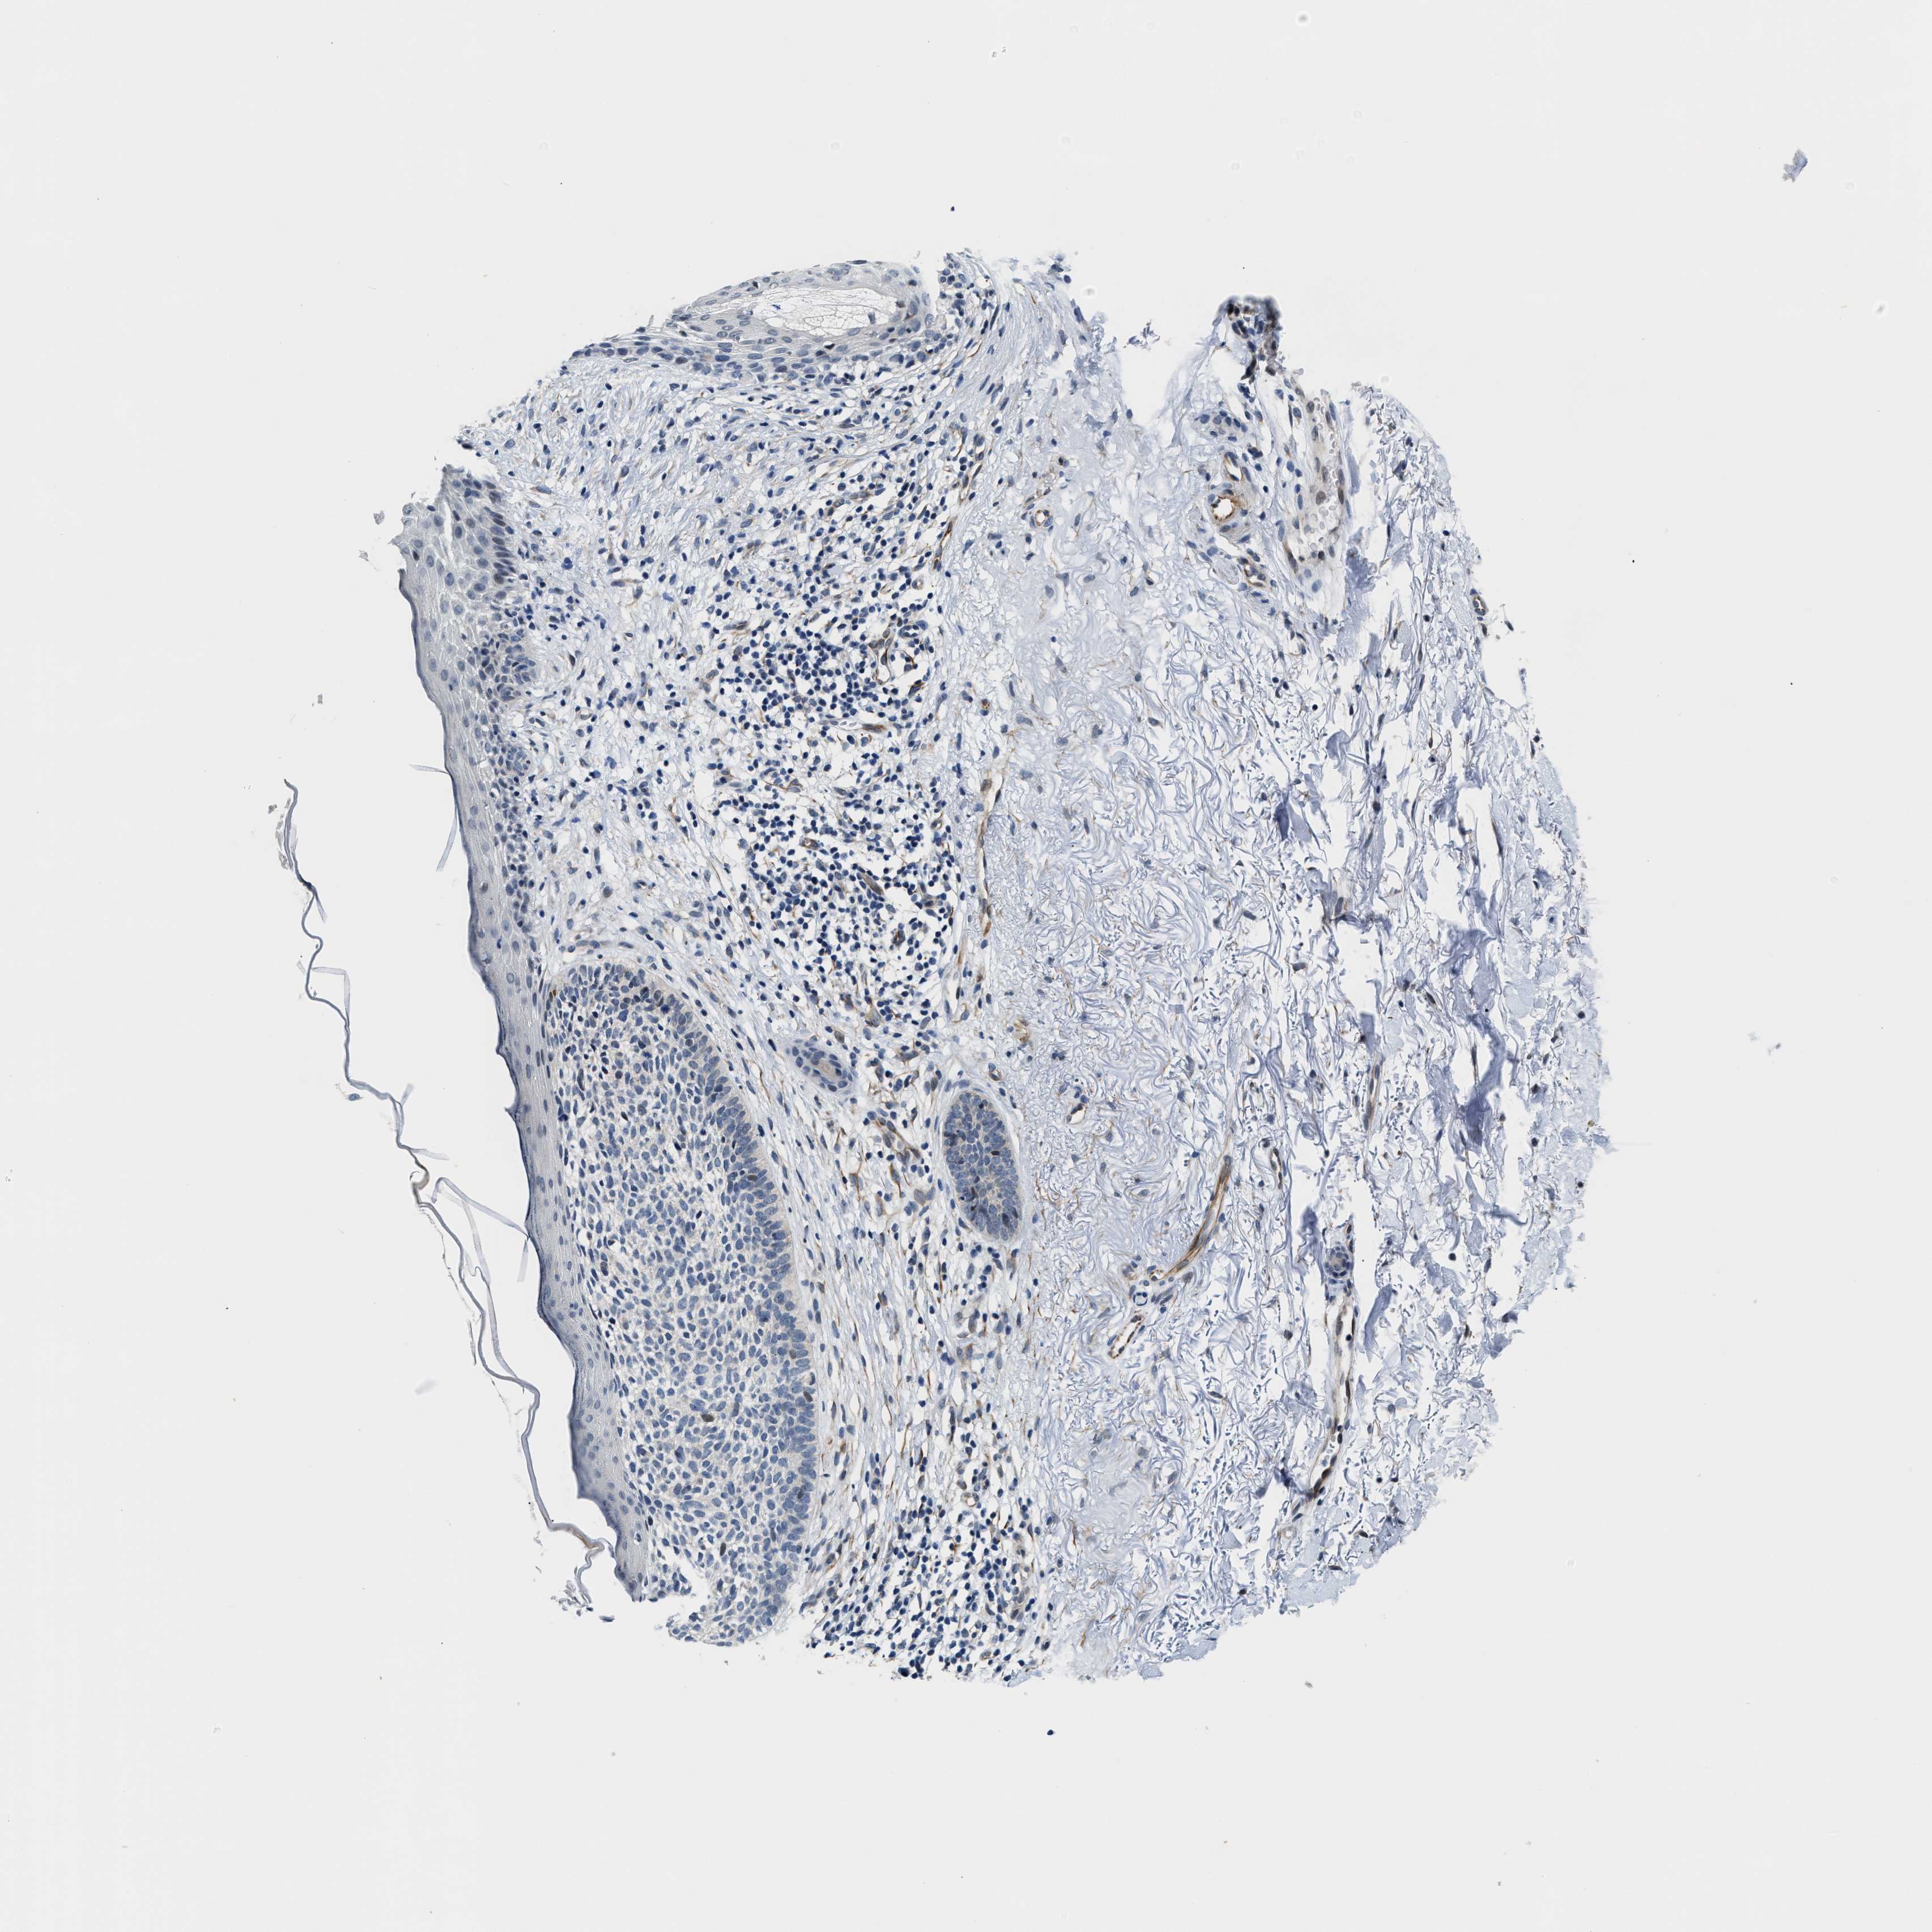

SKIN CANCER - Protein expressioni

A mouse-over function shows sample information and annotation data. Click on an image to view it in a full screen mode. Samples can be filtered based on level of antibody staining by selecting one or several of the following categories: high, medium, low and not detected. The assay and annotation is described here.

Antibody stainingi

Antibody staining in the annotated cell types in the current human tissue is reported as not detected, low, medium, or high, based on conventional immunohistochemistry profiling in selected tissues. This score is based on the combination of the staining intensity and fraction of stained cells.

Each image is clickable and will lead to virtual microscopy that enables deeper exploration of all samples and also displays staining intensity scores, fraction scores and subcellular localization as well as patient and tissue information for each sample.

Antibody HPA044244

Antibody HPA058777

Antibody CAB020694

Basal cell carcinoma